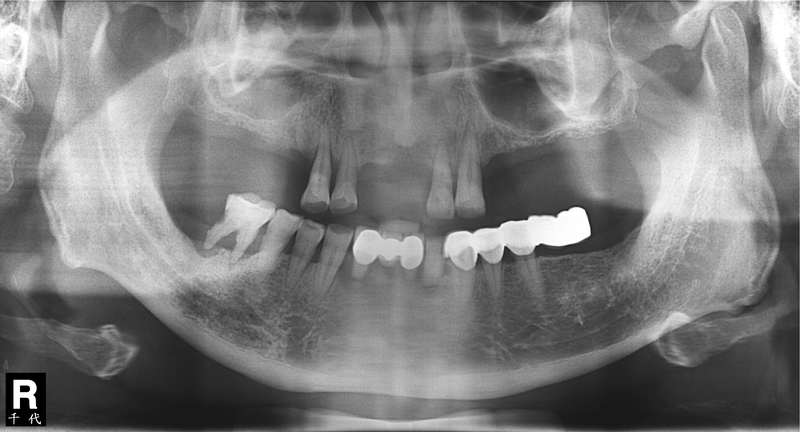

以下兩則All-on-4™座談會的微電影是由千代牙醫連鎖機構負責拍攝,而片中人物黃小姐及徐伯伯皆是本院林博川醫師種植All-on-4™全口重建手術的患者!由他們親自現身說法,希望能讓大家更加清楚的瞭解All-on-4™手術究竟有怎麼樣的魅力能讓缺牙的人趨之若鶩,藉由手術之後進而得到更美好的人生!!

第一則:千代牙醫連鎖機構 All-on-4 座談會-向營養不良說bye bye篇 黃小姐現身見證

第二則:千代牙醫連鎖機構 All-on-4 座談會-向活動假牙說bye bye篇 徐伯伯分享見證